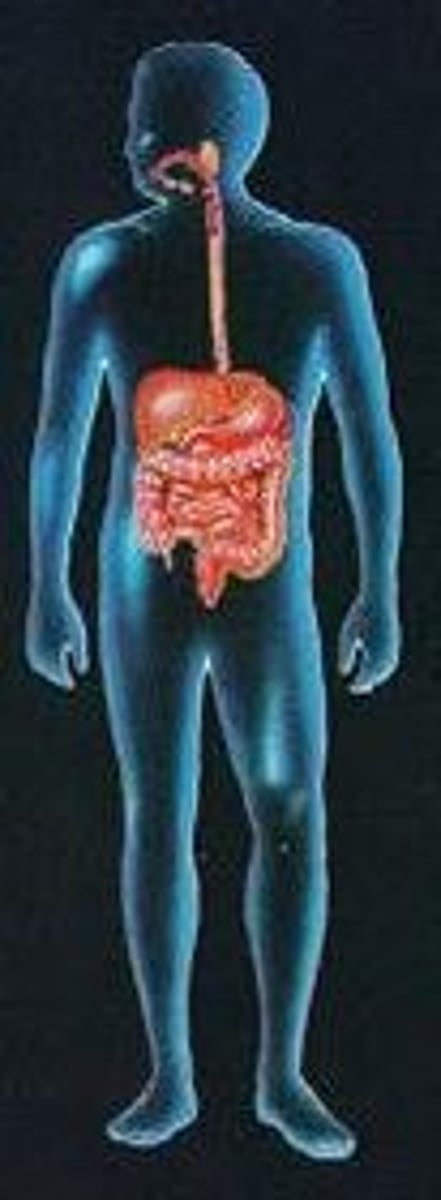

What is the digestive system?

consists of all organs from mouth to the anus involved in the ingestion and breakdown or processing of food.